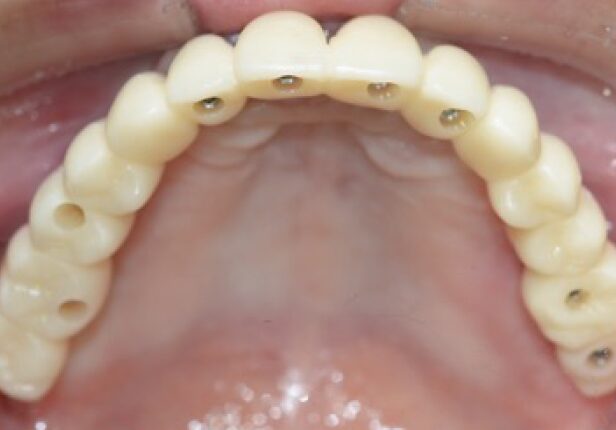

Mandibular Full case

Temporary Crown right after the placement (1st:: Shell)

Temporary Crown after 1 month (2nd)

Temporary Crown after 10 months